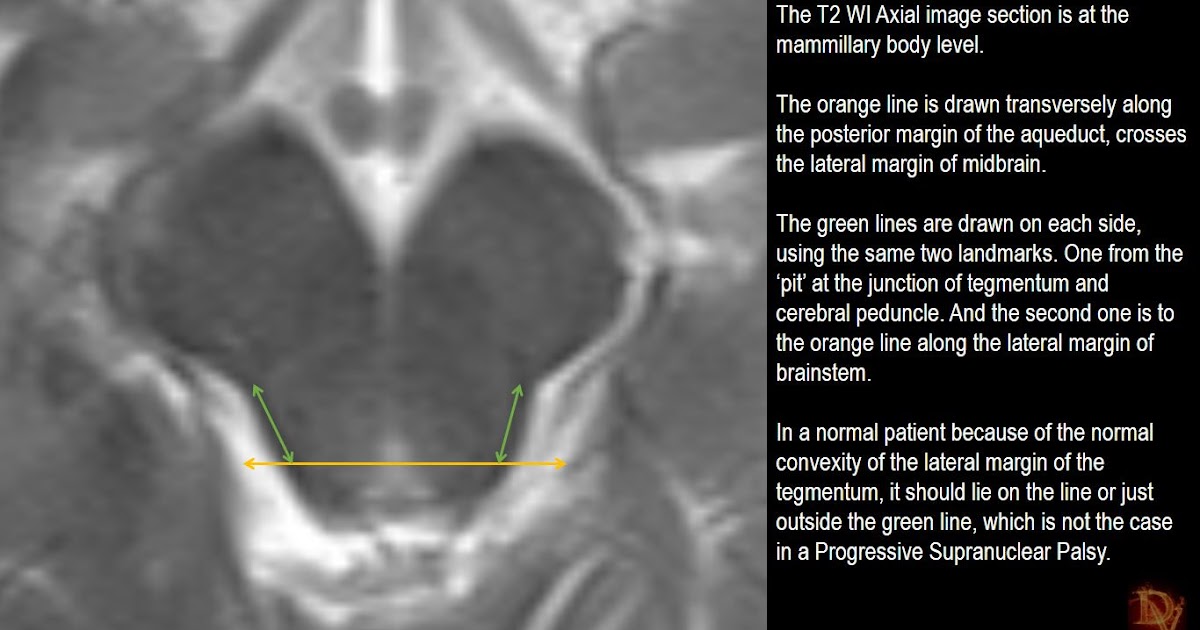

Psp Mri Brain Psp In Radiography to detect and determine image error and artefact types in intraoral. digital radiographs with photostimulable storage phosphor (psp). • describe the basic construction of a. our study discussed intraoral image artifacts that were characteristic of psp, where the most common artifacts. these include photostimulable luminescence (psl), storage phosphor radiography (spr), digital luminescence. On completion of this. Psp In Radiography.